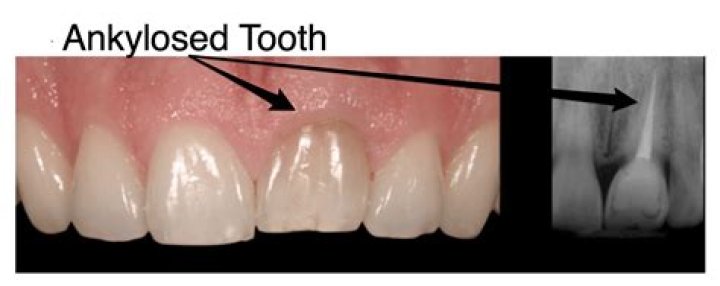

What do you mean by ankylosed tooth?

AnkylosisAnkylosis Ankylosis is a stiffness of a joint due to abnormal adhesion and rigidity of the bones of the joint, which may be the result of injury or disease. The rigidity may be complete or partial and may be due to inflammation of the tendinous or muscular structures outside the joint or of the tissues of the joint itself. › wiki › Ankylosis

Ankylosis - Wikipedia

occurs when a tooth fuses to the surrounding bone and slowly begins to sink or submerge into the nearby gum tissue. Normally, small fibers called the periodontal ligament hold a tooth in its socket, but with ankylosis, this connection is absent, and the tooth becomes directly attached to nearby bone.

How can you tell if a tooth is ankylosed?

An ankylosed tooth looks exactly like a regular tooth, except that sometimes it may be higher or lower in the gum line. A tooth can become ankylosed while it is still growing out of the gums. When that happens, the tooth is usually shorter due to its growth having been halted mid process.